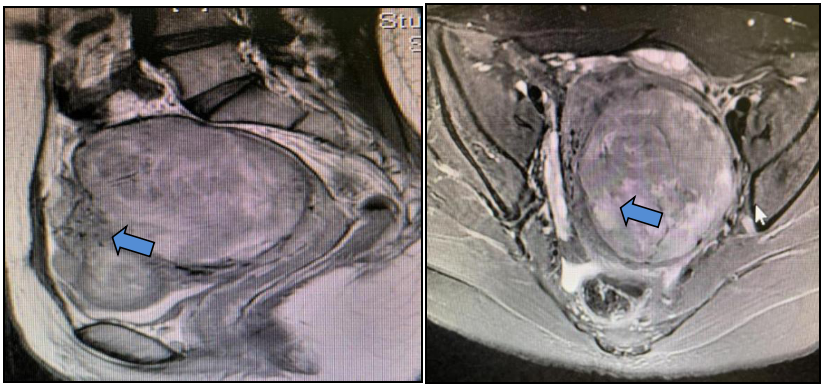

以“子宫肌瘤剔除术后14个月,子宫肌瘤复发11个月”再次返院就诊,盆腔增强磁共振成像(MRI)提示:子宫体大小约7.4 cm×6.8 cm×8.0 cm(含病变),子宫肌瘤大小约5.0 cm×4.8 cm×4.6 cm,突入宫腔,其内多发囊变,考虑子宫粘膜下肌瘤。

盆腔增强MRI提示子宫体明显增大,约9.2 cm×12.3 cm×9.5 cm(含病变),宫腔受压,子宫肌壁、黏膜下及浆膜下见多发结节及肿块(约10个),宫体前壁上段一结节突入宫腔,直径1.3 cm,最大者位于左后壁,大小约7.6 cm×7.9 cm×10.0 cm;DWI多发高信号,考虑子宫富于细胞型肌瘤,血供丰富,生长活跃。